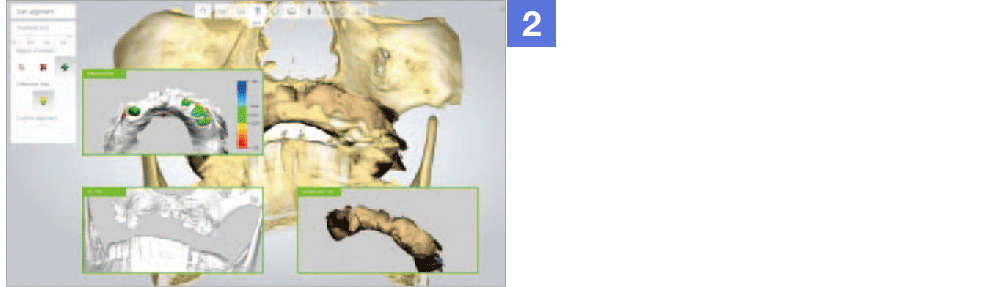

Through virtual operation procedure though 3D computer, DIO NAVI system decreases danger of implant surgery by checking patient's bone tissue and nerve position for planning the optimal surgery procedure and making customized surgical guide.

Through implant planning that considered occlusion and stress dispersion, DIO NAVI Digital Implant System increases the accuracy of the implant treatment and enabled 3D simulation that is used for patient counsel purposes.